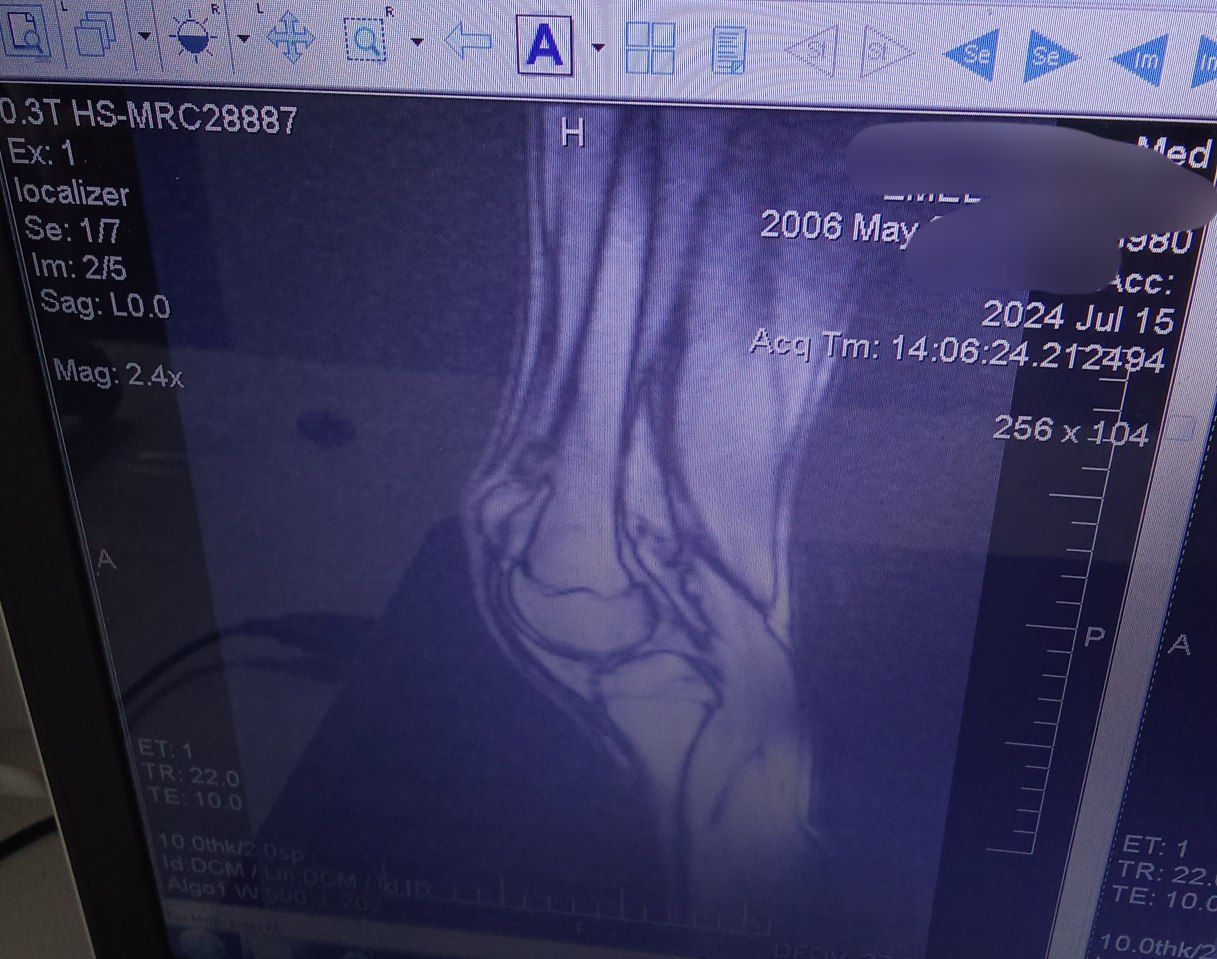

У меня такая же хуйня, но куда хуже, с рождения двухсторонняя дисплазия, в лет 11 началось проявление вальгусной деформации ног, спустя год стали вылетать надколенники (чашечки). С каждым годом это все ухудшалось и ухудшалось. Родители особо не торопились меня отводить к врачам, по этому к 14 я утратил способность нормально ходить (вечный страх что вот вот вылетит колено и я упаду) бегать я вовсе не могу, потому что надколенники сместились латерально кверху, по этому стабильность моих ног начинает качать уже от обычного ветра. Из за этого я не смог подписать контракт в 18 как и хотел, но начал процесс какого либо контакта с врачами и поиска решения проблемы без мам и пап. Сам выбивал справки и направления на бесплатные обследования. Спустя 4 месяцев сбора кучи обследования, пару рентгенов, пару мрт и одного торсиального кт. Мой хирург который взял меня под свое крыло, увидел во мне необычайно удивительный случай. Моментально уехал в Москву, там на какой то крутой конференции, он показал мои результаты обследований и видео подвижности моих ног другим врачам и как он передал, там все ахуели. Предложил мне относительно сложную операцию, типичная остеотомия, только пилить будут в двух местах бедро, в трёх большеберцовую кость и резекцию икры для предотвращения спазма нервов ну и замена связок на надколеннике. В итоге, мне остаётся букалаьно две недели до госпитализация и две недели и один день до операции. Я очень волнуюсь, потому что я забыл что уже такое бегать, что такое прыгать и ходить без страха вывихнуть колено.

IMG202507271253[...].jpg 97Кб, 577x1280

IMG202507271253[...].jpg 228Кб, 1280x960

IMG202507271253[...].jpg 195Кб, 960x1280

IMG202507271253[...].jpg 182Кб, 960x1280

IMG202507271253[...].jpg 183Кб, 1217x959

IMG202507271253[...].jpg 199Кб, 1224x892

IMG202410312014[...].jpg 25Кб, 299x781

IMG202507271253[...].jpg 126Кб, 1138x788